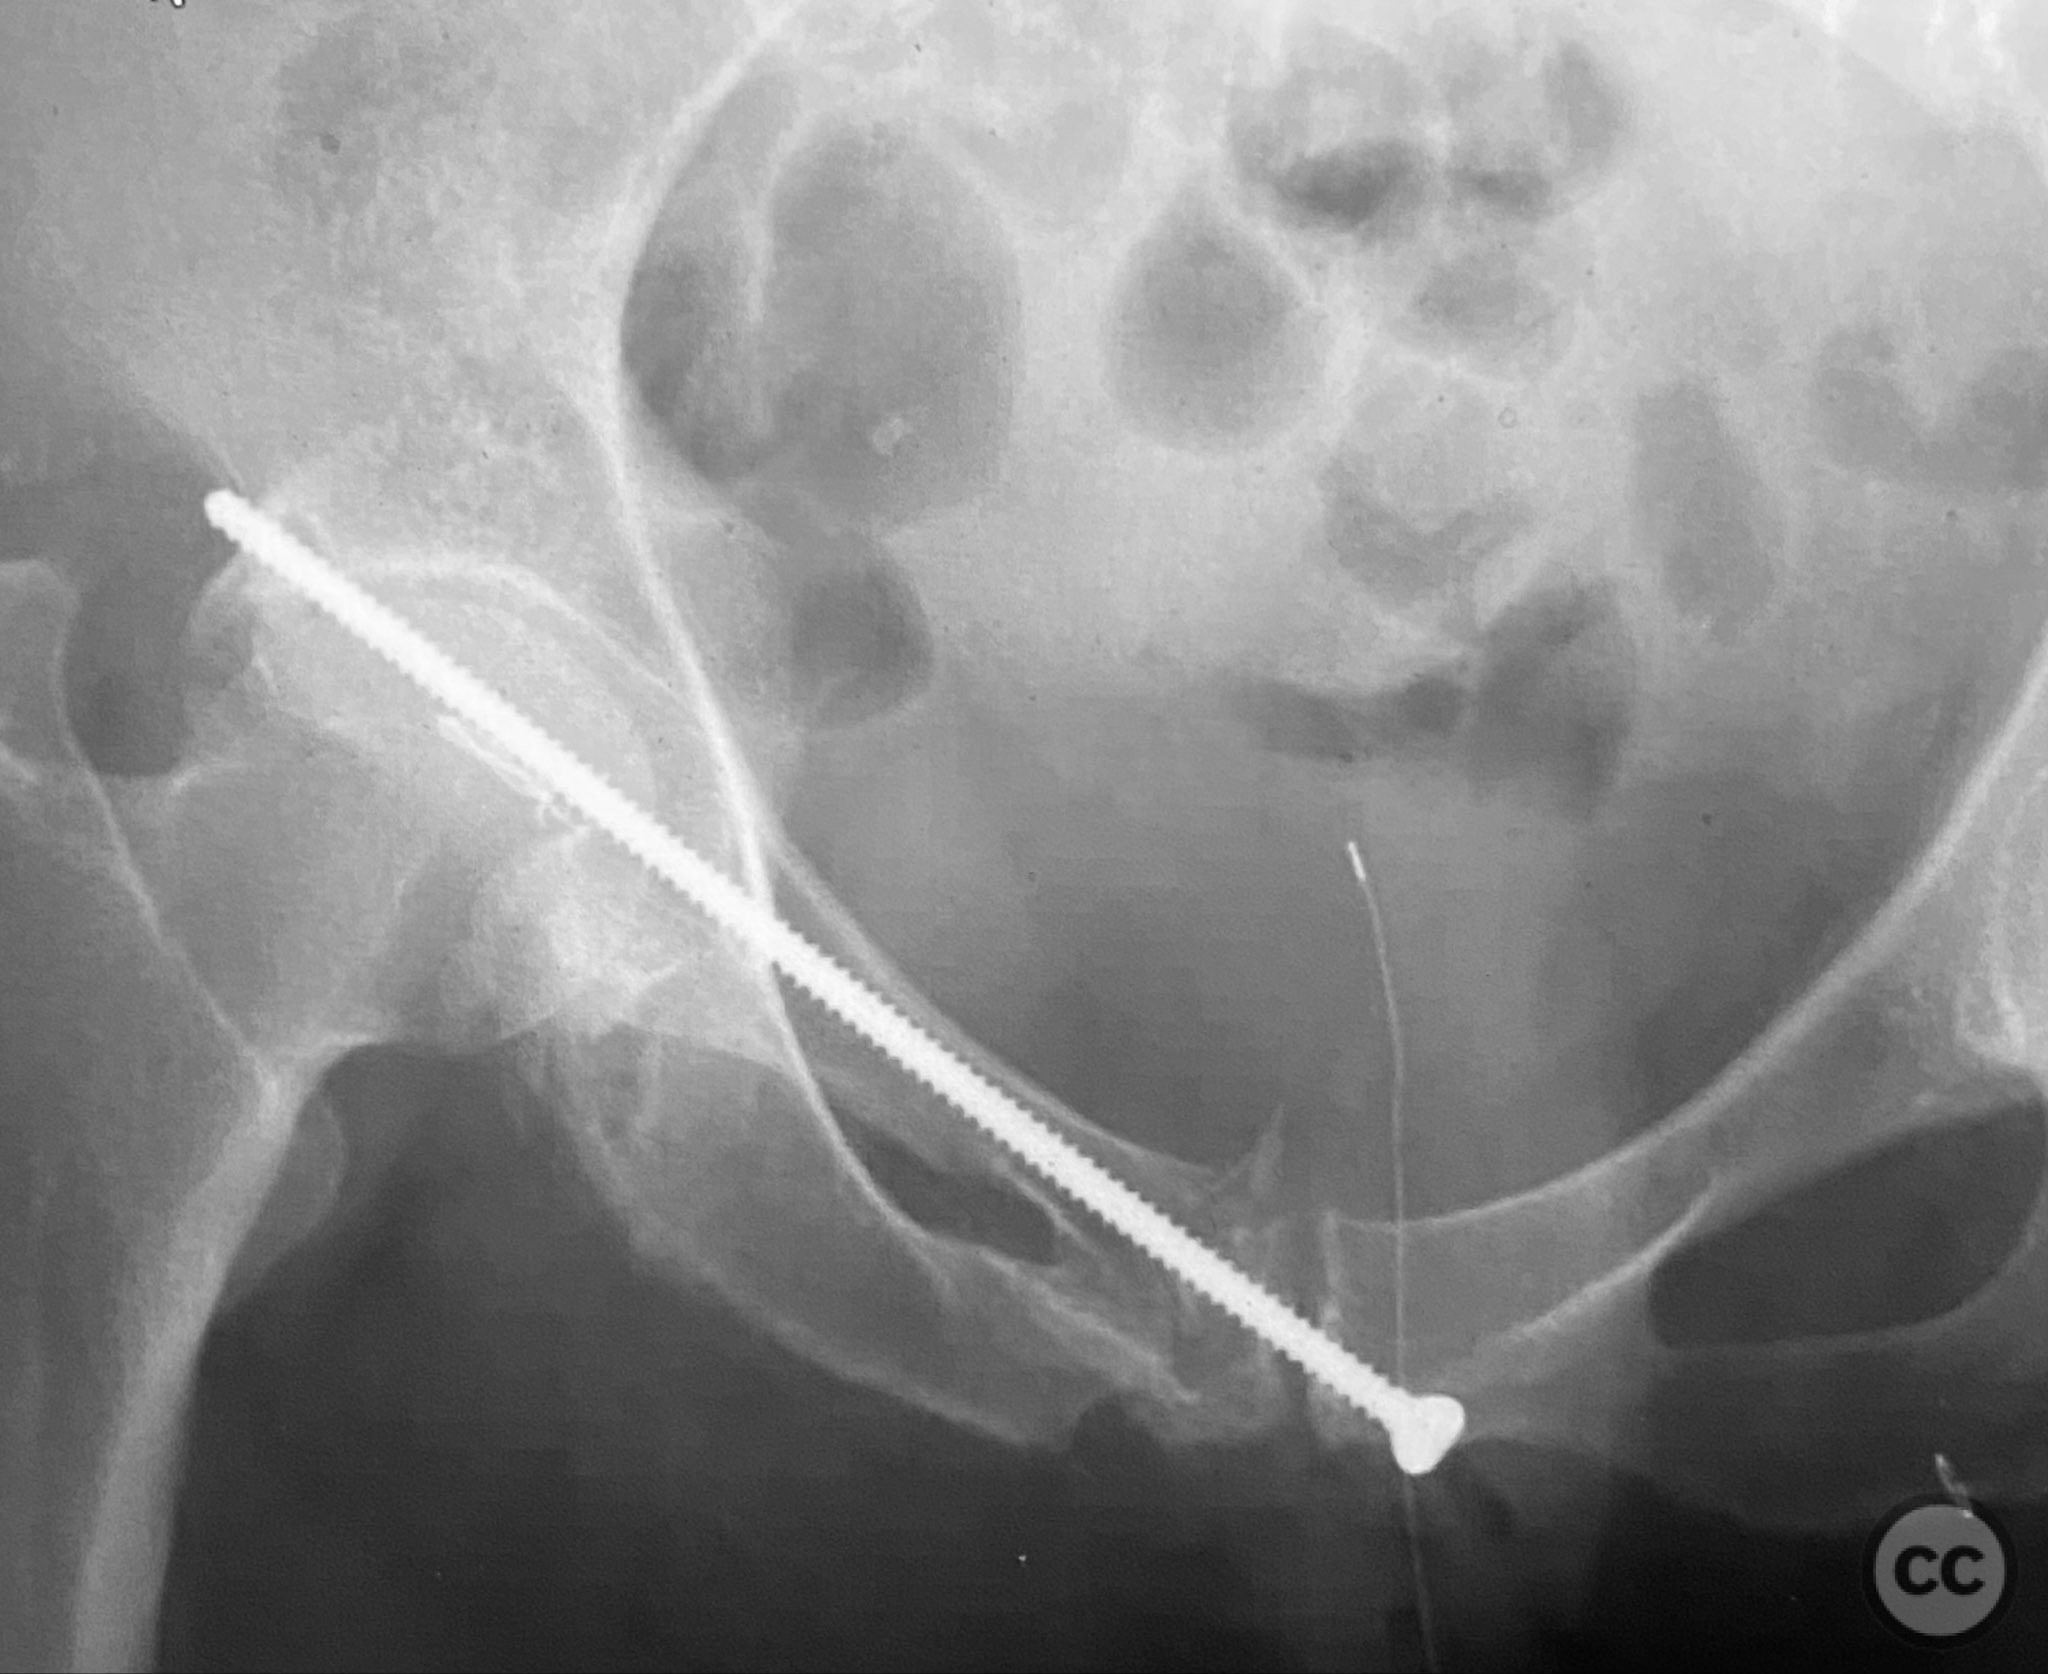

Intraoperatively, a 3.5mm drill was used through a protective sleeve to initiate the screw pathway across the superior pubic ramus. Due to poor bone quality, a 2.5mm drill was subsequently employed; however, resistance was encountered as the drill tip engaged the dense cortical apex of the anterior acetabular wall. The drill became lodged in this region. To avoid drill breakage, manual extraction using pliers was considered; however, the surgeon elected to carefully deflect and advance the drill manually, successfully completing the pathway. Screw length was measured directly from the embedded drill tip. A 4.5mm cortical screw was then inserted trans-symphyseally along the prepared medullary canal, achieving stabilization of the unstable ramus fracture. Postoperative CT confirmed appropriate screw trajectory and demonstrated the dense cortical bone at the anterior acetabular wall where the drill tip had engaged.

Orthopaedic implants used:   4.5mm cortical screw